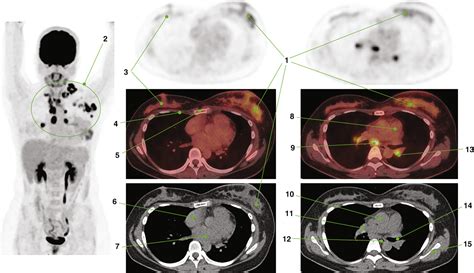

At its core, a Pet Ct scan is designed to provide both functional and structural information. While a traditional CT scan uses X-rays to create detailed pictures of organs and tissues, a PET scan uses a small amount of radioactive tracer to highlight areas of high metabolic activity. This is particularly crucial in oncology, as cancer cells often exhibit higher metabolic rates than healthy cells.

When these two technologies are combined into a single Pet Ct machine, the results are fused together. This allows doctors to pinpoint the exact location of a biological abnormality and observe its physical size and shape simultaneously. The fusion of this data is what makes it a gold standard in modern diagnostics.